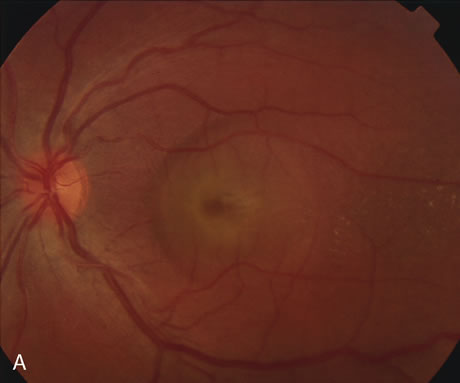

DIAGNOSIS Age-related macular degeneration (AMD) may be divided into two types. Nonexudative (“dry”) AMD has several morphologic forms, including “hard” discrete drusen, shallow retinal pigment epithelial detachments associated with thickened Bruch's membrane (“soft” drusen), and geographic atrophy (GA) of the retinal pigment epithelium (RPE).3 On FA the area of GA appears hyperfluorescent for window defect from the early frames of the angiogram, with late staining of the underlying sclera (Fig. 1). However, these pathologic changes can usually be assessed by clinical examination, and FA is generally not necessary to diagnose nonexudative AMD. An exception is cuticular drusen, which may appear clinically as a subtle disturbance of the RPE; FA reveals multitudes of small, discrete drusen described as “stars in the sky” (Fig. 2). The second type of AMD, which is associated with soft drusen, is known as exudative (“wet”) AMD. It is due to a choroidal neovascular membrane that has incompetent vessels resulting in detachments of the RPE and the neurosensory retina. Consequently, in patients with a large RPE and/or serous neurosensory detachment, FA is often necessary to rule out a choroidal neovascularization (CNV). In general, a small pigment epithelium detachment (PED) and a larger neurosensory detachment overlie CNV, while the opposite is generally the case in a nonexudative PED. Additionally, CNV often presents as a “notched” PED (Fig. 3).4 The presence of subretinal blood or pigment at the border of a PED strongly indicates that the detachment is exudative in origin (Fig. 4). Similarly, a rip in the RPE generally reflects subretinal fibrosis from a CNV (Fig. 5 and 6). The diagnosis is more difficult in patients who have a chronic, organized PED. Such a lesion may be due to either nonexudative AMD or to an organized, fibrotic CNV. Clinically and angiographically, it may be impossible to distinguish between these two conditions. In most cases, however, FA does assist in making the diagnosis.

In patients with a shallow neurosensory detachment, the Amsler grid test and visual acuity may be normal. If there is subtle elevation of the neurosensory retina on biomicroscopy examination, FA may demonstrate a CNV before it is symptomatic. It is often easier to evaluate both RPE and neurosensory detachments with good stereoscopic FA pictures than with direct examination.5 Consequently, FA can be helpful in determining the presence and extent of these processes. This is particularly important in patients with CNV due to AMD, because its aggressive course often requires prompt intervention to save central vision.6,7 Furthermore, FA helps in recognizing two types of CNV: classic and occult. Classic CNV consists of a well-defined neovascular membrane, which is apparent in the early phase of the angiogram and shows late leakage of dye beyond its boundaries (Fig. 7 and 8). Occult CNV is seen on by FA as an area of late hyperfluorescence of undefined origin or as a neovascularized PED (Fig. 9 and 10 ). Mixed-type CNV is predominately classic or minimally classic depending on whether the classic component is more or less than 50% of the entire lesion (Fig. 11).